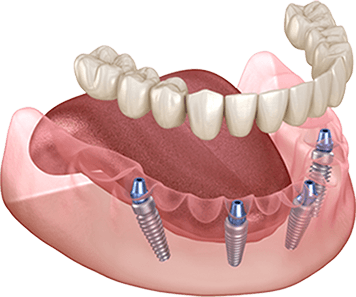

オールオン4 All-on-4

オールオン4は、4本のインプラントで上顎または下顎の人工歯列を支える方法です。従来の多数本インプラントよりも少ない本数で治療できるため、身体的負担や治療期間、費用を抑えられることが特徴です。

オールオン4では、インプラントを斜めに埋め込むことで噛む力を広く均等に分散し、最小4本のインプラントで上顎または下顎の全ての人工歯を支えることができます。日帰りで手術が可能なため、患者さまの身体的な負担も軽減され、手術当日に仮歯を装着できます。わずか1日で口元の機能と見た目が改善され、これまでの歯に関する悩みから解放されます。多くの歯を失った患者さまにとって、治療にかかる時間や費用、身体の負担を最小限に抑えながら、安定した噛み心地と自然な見た目を実現できる治療法です。